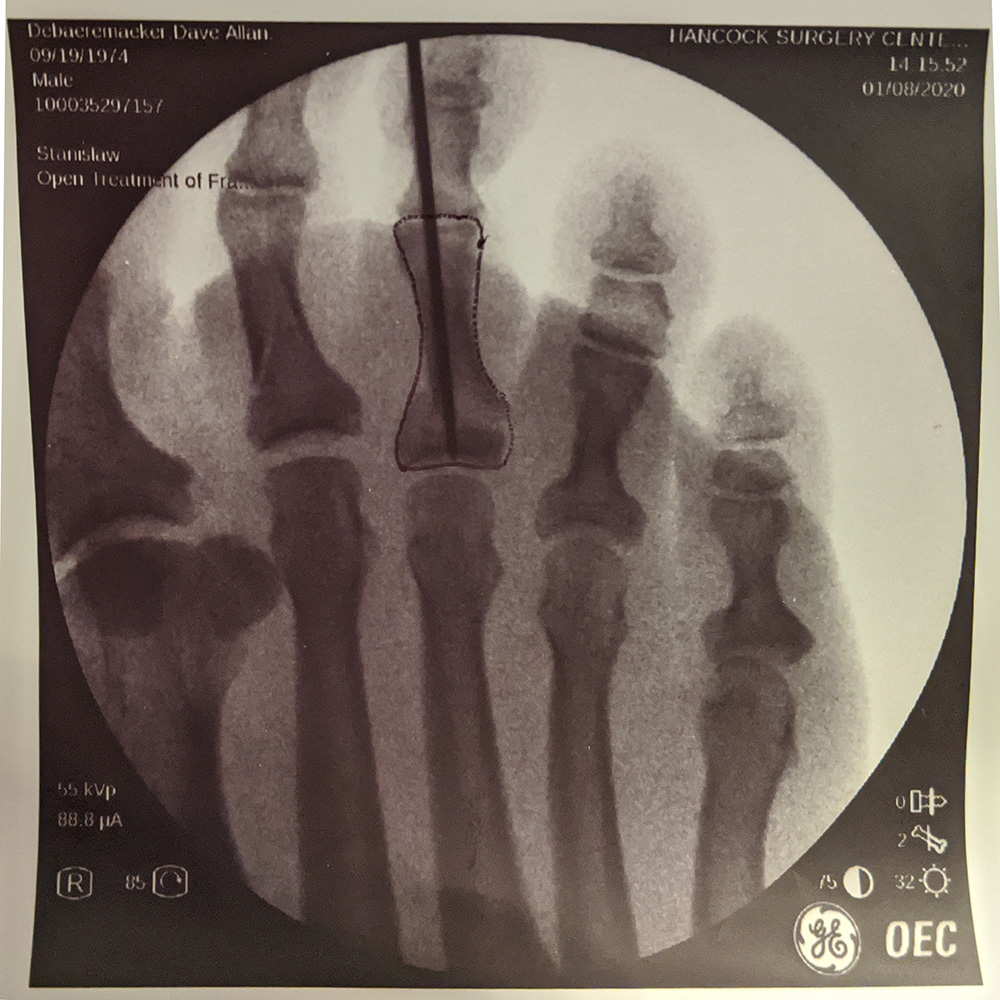

So shortly after I got to my feet, my wife drove me to the emergency room of the local hospital. X-rays confirmed that I indeed had two broken toes. (My first bone break ever - I am so proud) One had a simple crack, the other misshapen one was broken clean in half. The doctor straightened the middle one, taped me up, and sent me on my way. He did suggest that I go see an orthopedic surgeon to look at the middle toe.

The emergency room gave me my x-rays on CD-ROM, so a family doctor friend offered to drop by the house on Friday to take a look at my x-rays for a second opinion. Once I downloaded a viewer for the images I quickly realized that I actually had a third broken toe. So the 2nd and 4th toe had cracks, and the third was a clean break.

The orthopedic surgeon looked at my foot on Monday and his first comment was "Yep, you broke 4 toes." Its a well documented myth that vaccines cause autism, but apparently every time I see a new doctor I break another toe! After closer examination it was determined that the 4th "break" was likely an old injury, or an x-ray smudge.Never been more relieved to only have 3 broken toes!

So surgery was booked for Wednesday (yesterday).

So the surgery was pretty simple, and pretty unremarkable as things go. I left the house at 9:30, and returned at 2:30. I was under general anesthetic for about an hour.

The surgery was to have a pin inserted into my middle toe to keep it stable to give the bone a change to heal cleanly. However it also means I am basically not allowed to put any weight on my right foot, and keep it elevated as much as humanly possible.Annoyingly I am actually less mobile that I was before the surgery. This is actually mentally very hard to deal with. Previously I could get into my studio and be creative, and do things. Now I am stuck upstairs, and really limited to the bed or the couch.